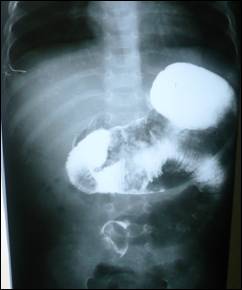

gastrointestinal contrast study showed obstruction in proximal jejunum (Fig. 1).

Figure

1: GIT contrast study showing obstruction and filling defect in the proximal

jejunum